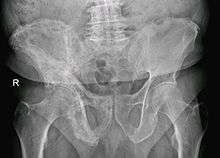

Paget's disease of bone (also termed ambiguously, just Paget's disease) is caused by the excessive breakdown and formation of bone, followed by disorganized bone remodeling. This causes affected bone to weaken, resulting in pain, misshapen bones, fractures and arthritis in the joints near the affected bones. Rarely, it can develop into a primary bone cancer known as Paget's sarcoma. Often Paget's disease is localized to only a few bones in the body. The pelvis, femur, and lower lumbar vertebrae are the most commonly affected bones. Paget's disease typically is localized, affecting just one or a few bones, as opposed to osteoporosis, for example, which usually affects all the bones in the body.

The outlook is generally good, particularly if treatment is given before major changes in the affected bones have occurred. Any bone or bones can be affected, but Paget's disease occurs most frequently in the spine, skull, pelvis, femur, and lower legs. In general, symptoms progress slowly, and the disease does not spread to normal bones. Treatment can control Paget's disease and lessen symptoms, but is not a cure.